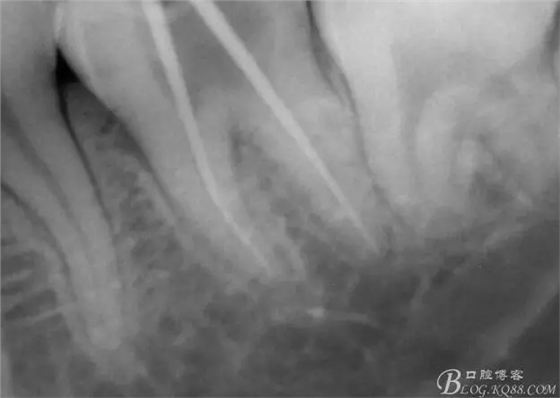

一周后復(fù)診,37叩(—)。去除暫封物,沖洗,試主尖拍片。

X線示牙膠尖到達(dá)工作長度,故行AH-PLUSH糊劑配合卡瓦熱牙膠機(jī)運(yùn)用連續(xù)波充法根充,暫封拍根尖片。